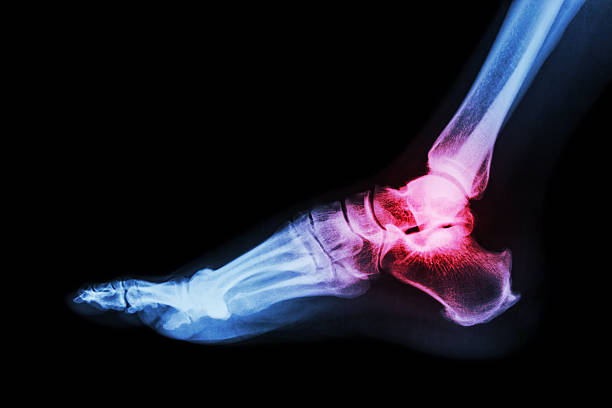

2. 외과 골절

발 관절이 강하게 바깥쪽으로 비틀어지게 되면 거골에 밀려 외과골절이 발생할 수 있고, 이는 나선형으로 꺾이는 경우가 많습니다. 뼈가 어긋남이 없다면 깁스등의 보존적 치료가 가능하며, 어긋남이 심하다면 플레이트와 나사등을 이용하여 고정하는 수술을 할 가능성이 있습니다.